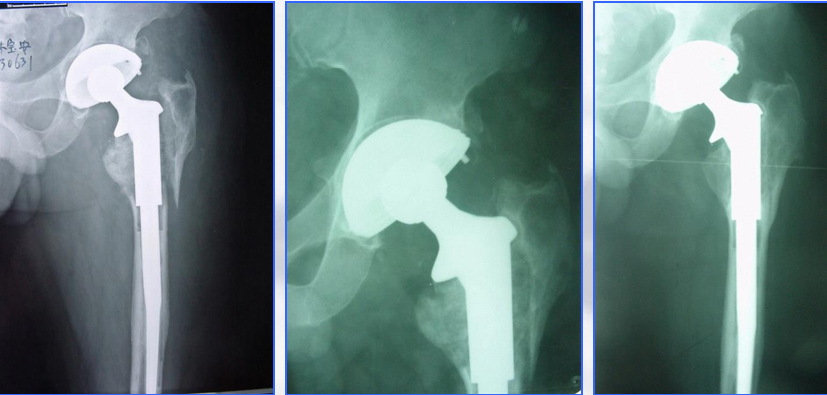

髓内固定:(二)翻修术

①适应征:假体松动的骨折

②原则:

尽可能的保留骨量

尽可能使假体与完整的宿主骨之间获得牢固固定

③假体的选择

长柄远端固定非骨水泥型

假体的长度至少要超过骨折端两倍于股骨直径的距离

骨缺损者,联合异体皮质骨板髓外固定